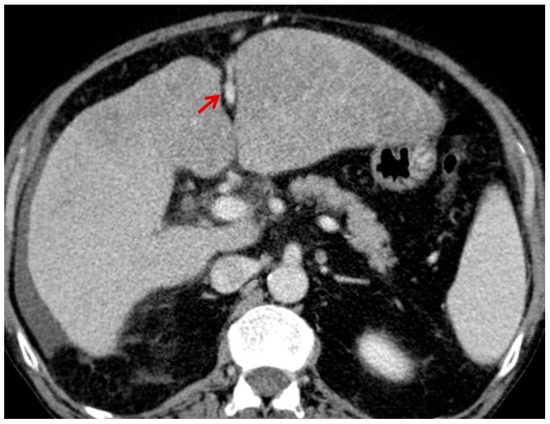

For this study, the images were retrospectively analyzed in consensus by two readers with experience in the field of abdominal imaging. The two readers assessed the following CT features: (1) The presence or absence of paraoesophageal varices and the size(mm) of the largest varix (Figure 1); (2) the presence or absence of paragastric varices and the size (mm) of the largest varix (Figure 2); (3) the largest diameter of the left gastric vein (Figure 3); (4) the presence or absence of splenorenal shunts and the size(mm) of the shunt (Figure 4); (5) the presence or absence of a repermeabilized round ligament and the size(mm) of it (Figure 5).

Figure 2. Axial contrast-enhanced CT shows enlarged paragastric varices (red arrow).